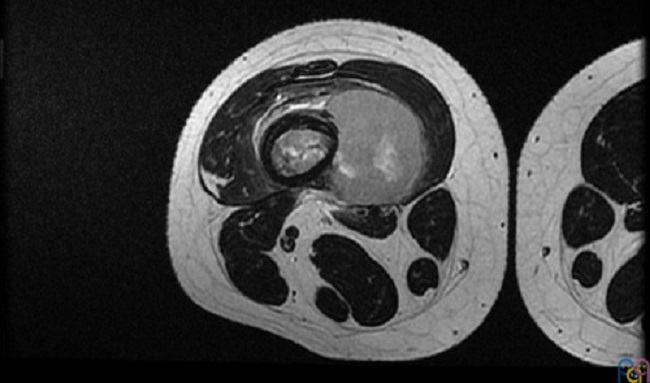

Se realiza traslado a hospital de referencia para ingreso en Unidad de Oncología. A su ingreso se amplía el estudio de la lesión realizando una resonancia magnética (Fig. 2 y Fig. 3) y estudio de extensión con tomografía computarizada pulmonar confirmándose la sospecha de tumor maligno óseo y metástasis pulmonares. Posteriormente se toma biopsia de dicha lesión guiada por ecografía confirmándose el diagnóstico de osteosarcoma.